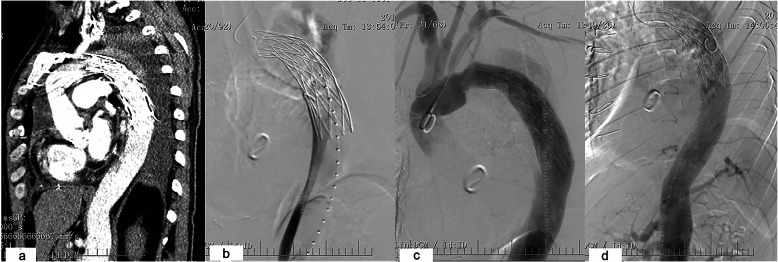

One patient had failed TEVAR, because the elephant trunk was inserted into the false lumen. Aortic angiography showed the true lumen was constricted and very small. Blood flow in main vessels of the abdominal organs was normal. The descending aorta was not enlarged, and the patient had no complaint (Fig. 2). Follow-up is still going on. Further intervention will be performed later. His data are not shown in Table 2.

Fig. 2.

a The elephant trunk was found in the wrong place based on CT. b In the angiography of the femoral artery, the true lumen was constricted and very small. c Trunk in the false lumen. d The blood supply of abdominal organs was from the false lumen